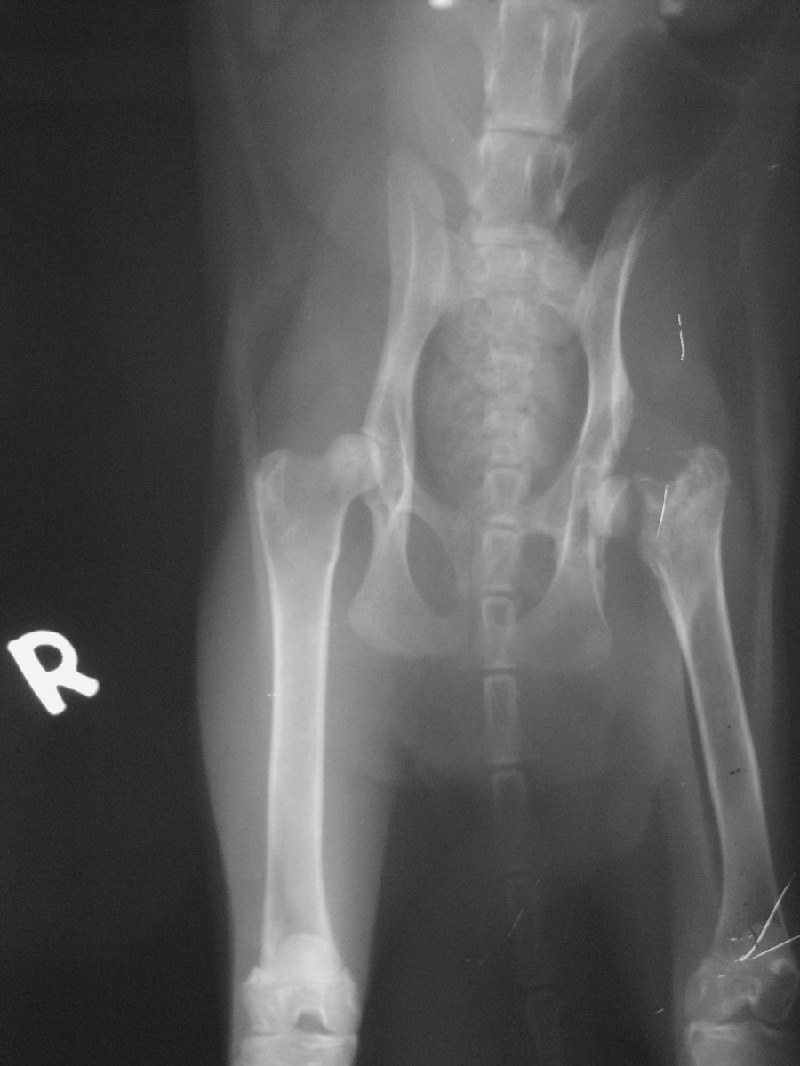

主題: 被車撞 下顎開放性骨折 大腿斷掉 申請者姓名: WanLin Lu 花色: 申請日期: 2014-03-11 02:05:57 申請者部落格: 申請者臉書網址: 所在縣市/合作醫院: 高雄市/樂生動物醫院 治療費用: 30800元 需求人數: 33人 已結案 (2014-05-18 09:39:58) 報名人員: Annisui Strauss(已付款)、Amberger(已付款)、JasmineC(已付款)、Jessica C. Chang(已付款)、Ameimei Wang(已付款)、黃安妮(已付款)、李子均 x2(已付款)、王大咪(已付款)、setona x2(已付款)、愛兒(已付款)、Mia Chao(已付款)、呂嘎嘰 x2(已付款)、白婷(已付款)、Fang-ching Lee(已付款)、Naima(已付款)、Helen Yu(已付款)、Irene Lin(已付款)、Katilin Chang、Chen Ping(已付款)、vivian(已付款)、喵卡(已付款)、Milkbau Lu(已付款)、仲希妍(已付款)、洪淑妍、錢快來 x2(已付款)、為流浪動物祈福(已付款)、小四 x3(已付款)、游銘威、蝦(已付款)、Jye-Lin Hsu(已付款)、 候補人員: 動物病情說明: 1/9 看到小花出現討吃的時,嚇了一跳,整個臉,前肢濕了又乾,

緊急送去醫院檢查後,她的左下顎粉碎性骨折,左股骨頸斷裂及感染的問題,有脫水及肝指數偏高的現象,所以馬上吊點滴治療。

後在2/14動了股骨頭摘除手術。